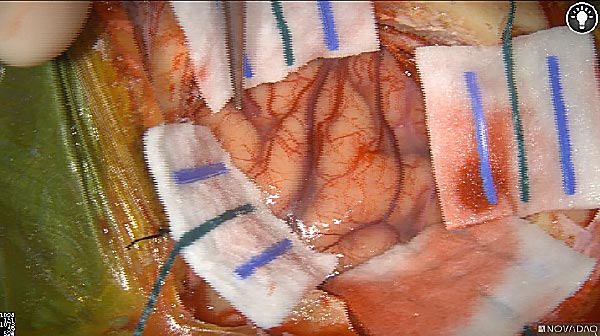

Primary tumor prior to resection

Fluorescence imaging of the tumor was performed prior to resection and after resection to “check” the wound bed. In the upper row the tumor is clearly visible with fluorescence and in the bottom row you can see that the wound bed is empty – there is no suspicious fluorescence left. The middle column of tiles show the fluorescence signal in black and white where the “white” represents the tumor and the black the background (= no fluorescence signal). The right column of tiles shows the overlay of the brightfield photo (in greyscale) and the fluorescence (red-yellow-blue heatmap). This image provides anatomical context to the surgeon – the surgeon can see where is the fluorescence located with regard to the tumor area.

White light

Fluorescence (heat map)

Fluorescence (black and white)